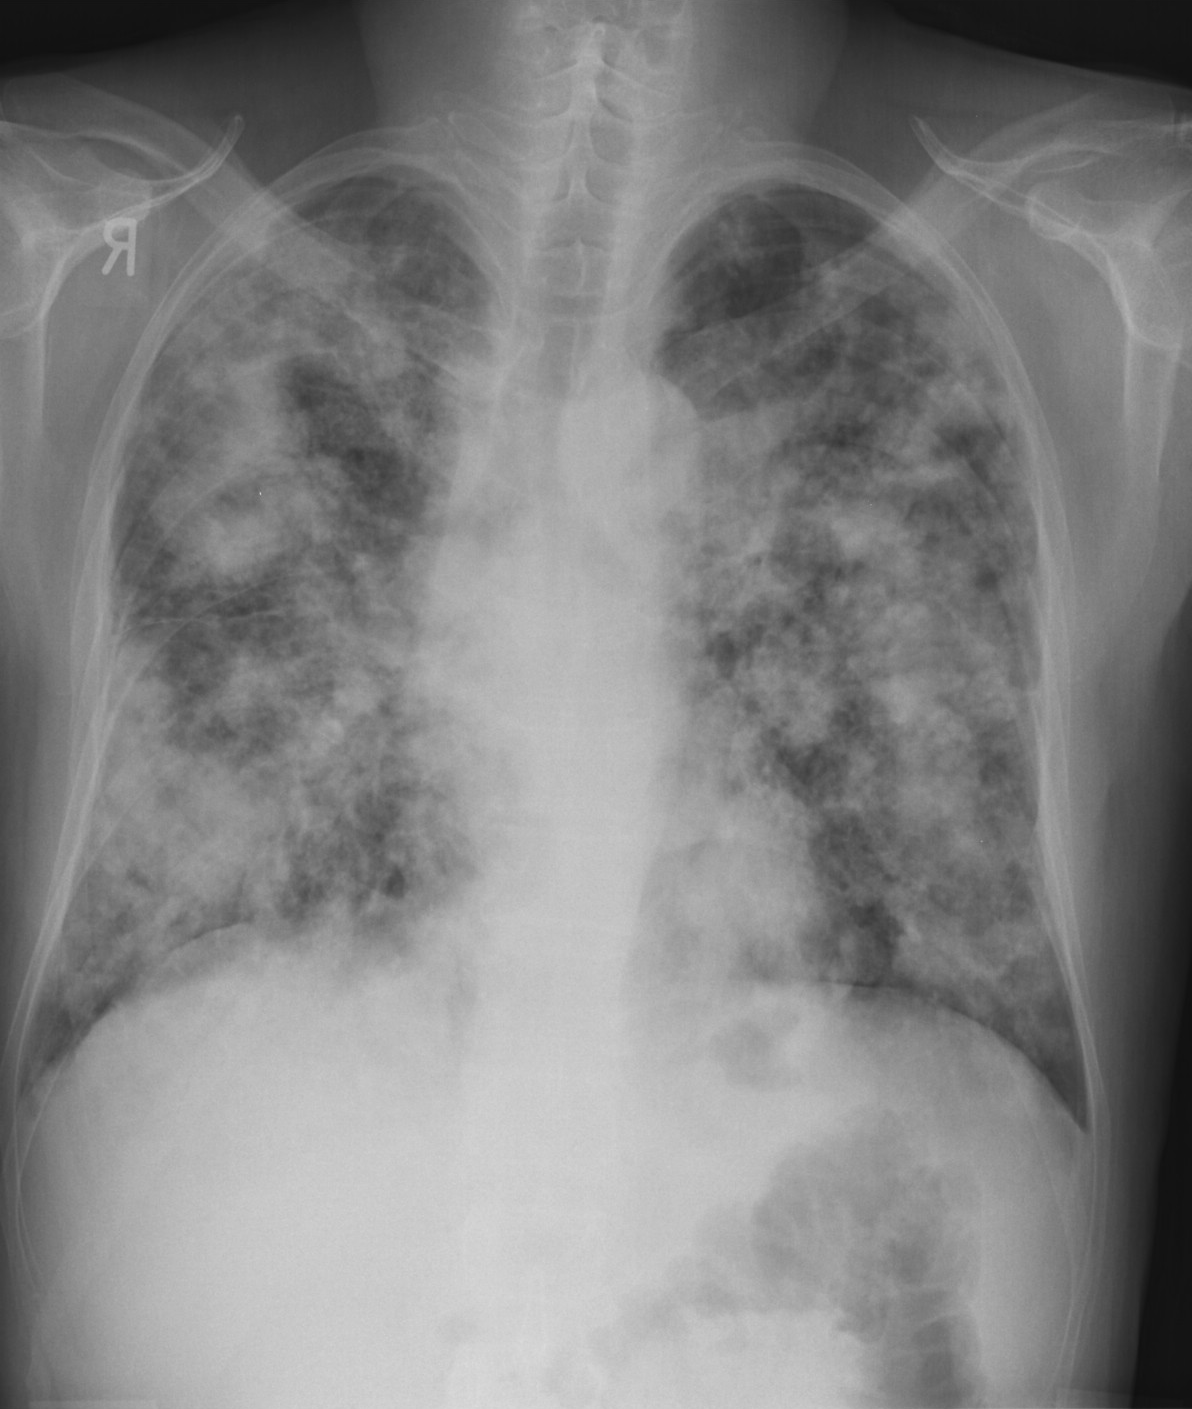

19. Tuberculosis, bidirectional chest radiographs and HRCT. (coronal reconstruction)

75 year old man: hx of hypertension, smoking. Symptoms: dyspnea, productive cough. Moist rales of auscultatory findings above the LLL, tension irritability in the level of lower dorsal spine.

a.) Chest radiograph, bilateral: Mild increased vascular markings. Extensive patchy lobar infiltration in the RUL Previous TB specific lesions in the left apex. The diaphragm contour is blurry on the right side (appr. 4 finger-wide pleural effusion). Cardiomegaly. Medium large dilated sclerotic aorta.

b.) HRCT: Reticular pattern of 10x10x5 cm area in the right apex (1st segment), (septal thickenings), mosaic-like ground glass opacity in the righ apex. Subpleural total atelectasis (mainly 1st segment): irregular mainly nodular soft tissue streak associated with the pleura (max. appr. 1 cm thickness). Some tiny subpleural emphysematous bullae in the right apex.